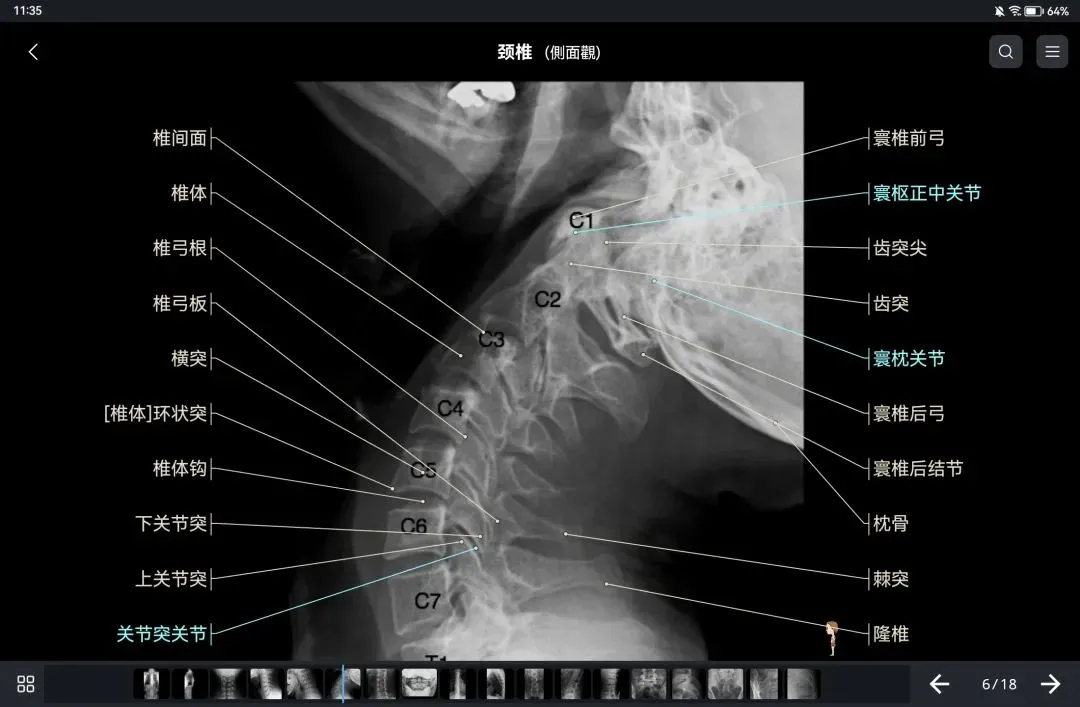

覆盖了X光、CT、MRI、断层大体解剖、核医学、介入造影、医学插图等多个模块,覆盖全身各个系统的影像解剖(正常解剖结构,无病例),其中的解剖结构高达87万个,结构标注超精细,超高清图像,历时两年研发设计完成✅。